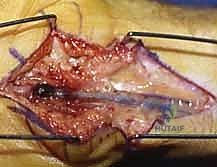

When excising a venous malformation or cavernous hemangioma, the lesion will appear as a spongy, purplish mass intimately intertwined with the surrounding fascia, tendon sheaths, or neurovascular bundles. Bipolar electrocautery is the instrument of choice; monopolar cautery risks thermal injury to adjacent nerves. The dissection proceeds circumferentially, utilizing a "peanut" sponge or fine tenotomy scissors to gently sweep normal tissue away from the pseudocapsule of the malformation. Feeding vessels are meticulously skeletonized, ligated with fine silk or metallic clips, and divided. If the malformation infiltrates a digital nerve (a common scenario), an operating microscope is brought into the field, and an epineurotomy is performed to dissect the vascular channels away from the nerve fascicles, accepting a subtotal resection if total excision would result in permanent anesthesia.

The management of acquired aneurysms (e.g., ulnar artery aneurysm in hypothenar hammer syndrome) or localized AVMs demands vascular reconstructive capabilities. Proximal and distal vascular control is obtained using vessel loops. The aneurysm is mobilized, and the ulnar nerve is carefully protected. If the Allen test confirms excellent radial collateral flow, simple ligation and excision of the aneurysm may be performed. However, to prevent cold intolerance or claudication, vascular reconstruction is preferred. The diseased arterial segment is resected until healthy intima is visualized. If a primary end-to-end anastomosis cannot be achieved without tension, a reversed interposition vein graft (typically harvested from the distal forearm or dorsal foot) is utilized. The anastomosis is performed under the microscope using 8-0 or 9-0 nylon sutures, and patency is confirmed intraoperatively with a micro-Doppler probe and the Acland strip test prior to closure.